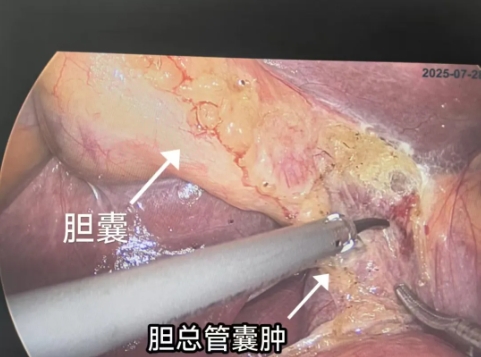

最终入院后确诊为先天性胆总管囊肿Ia型,我院肝胆外科卢明柱主任团队为患者提供了详细的治疗方案——微创手术切除畸形扩张的胆管,该手术创伤小,恢复快,疗效确切,单女士欣然接受手术方案,并于近日实施了手术(腹腔镜下胆总管囊肿切除+胆囊切除+肝总管空肠Rou-en-Y吻合)。目前,单女士术后恢复良好,已顺利出院。

切除囊肿:微创手术开始时,先在肚脐上方切开1cm皮肤,建立气腹;采用5孔法(见示意图),探查腹腔后先行切除胆囊。随后暴露胆总管囊肿位置,确定为先天性胆总管囊肿Ia型,然后游离先天性胆总管囊肿囊壁,同时游离出肝固有及肝右动脉,下界至胰腺段胰胆汇合上方结扎离断,沿门静脉脉前壁游离胆总管囊肿上界至肝总管,结扎离断切除胆总管囊肿。

胆道重建:切除囊肿需进行胆道重建,恢复消化功能。术中采用肝总管空肠Rou-en-Y吻合,距屈氏韧带20cm处闭合器离断空肠,远端经结肠后行肝总管空肠缝合;距肝总管-空肠吻合口60cm处行空肠-空肠侧面和侧面吻合。

成功开展腹腔镜下胆总管囊肿切除需要专业肝胆外科团队和麻醉科的精密配合。此次手术对操作要求极高,需要行两次消化道重建,分别是胆道和肠道吻合,肠道和肠道吻合,且流程复杂、步骤精细,手术精度直接决定了疗效和安全性。